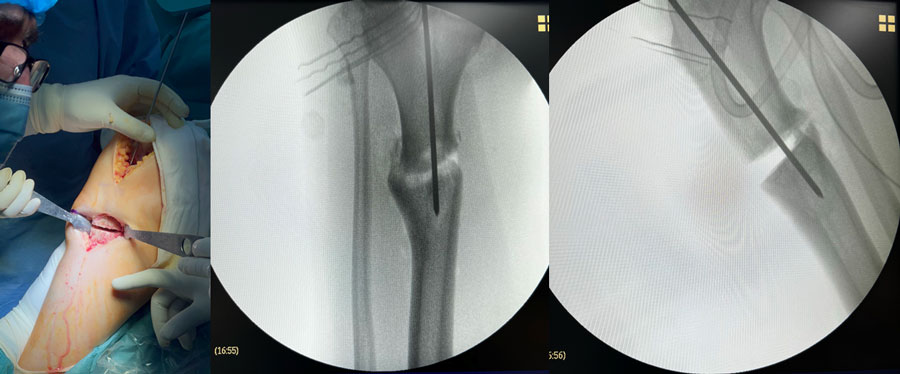

Final strategy decision: Tibial osteotomy by endomedular nailing, Unicompartmental medial knee replacement

Management of a post-traumatic knee pain: Intra-operative images

Intra-operative images